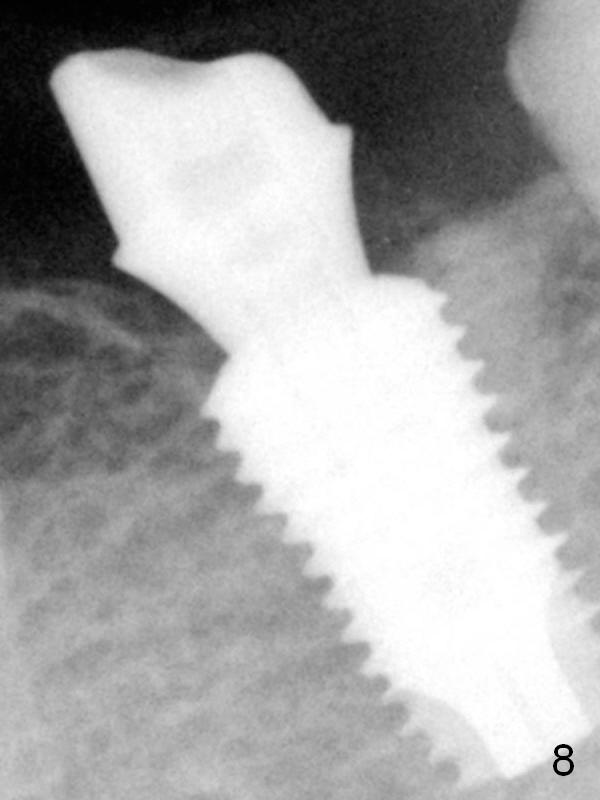

The patient returns for restoration 13 months postop with implant osteointegration (Fig.8).  The lamina dura-like structure forms between the cortex and the coronal first thread.